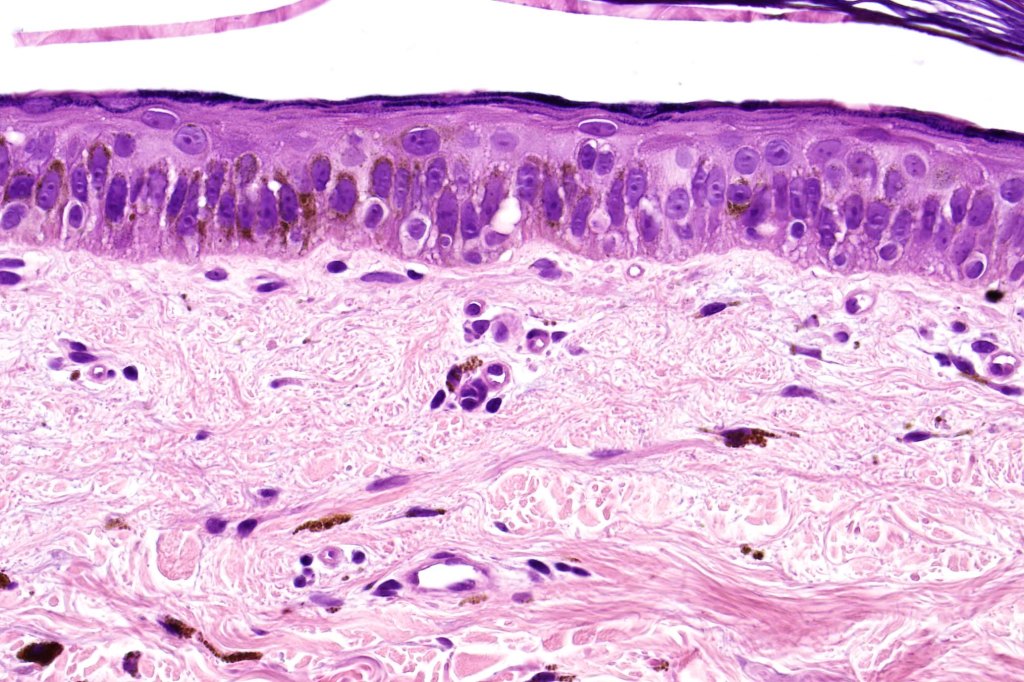

Differential diagnosis

A high power view of an atrophic, actinitc keratosis posted on McKee Derm by Dr. TòngTrần is shown below for comparison. There is very obvious nuclear pleomorphism & suprabasilar involvement..